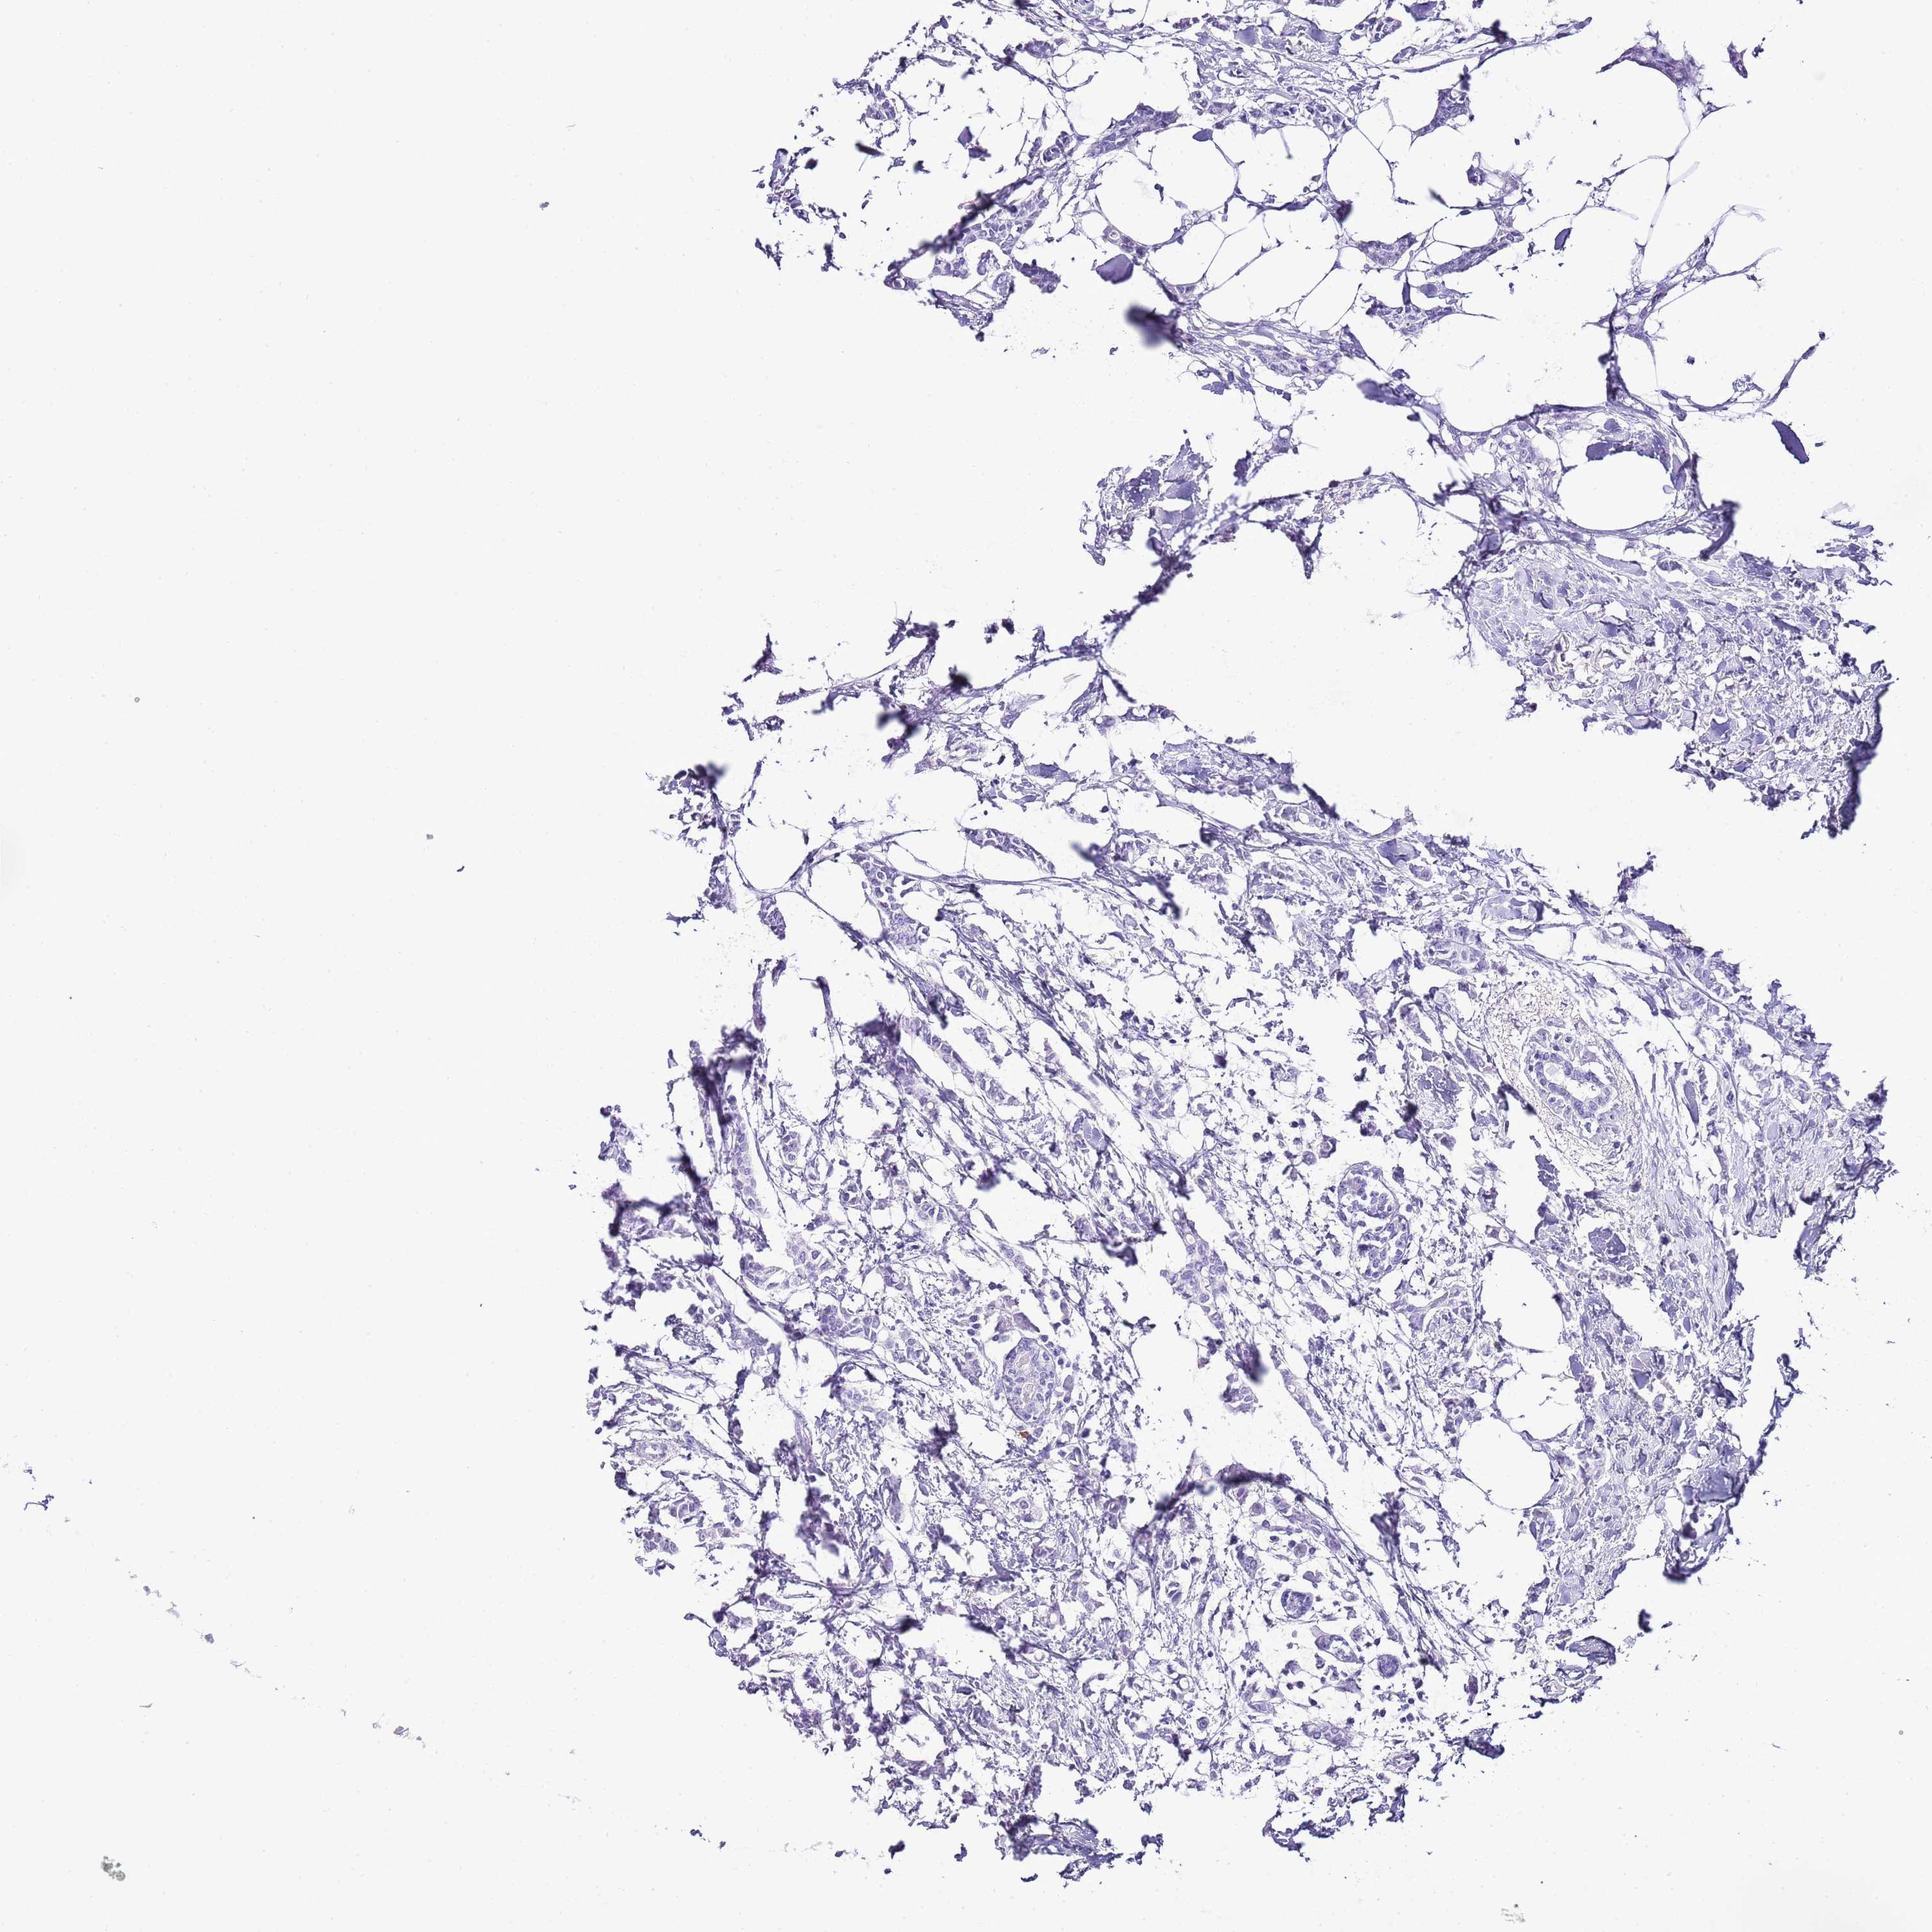

CANCER BREAST CANCER Show tissue menu

Breast cancer

Human cancer

Breast invasive carcinoma